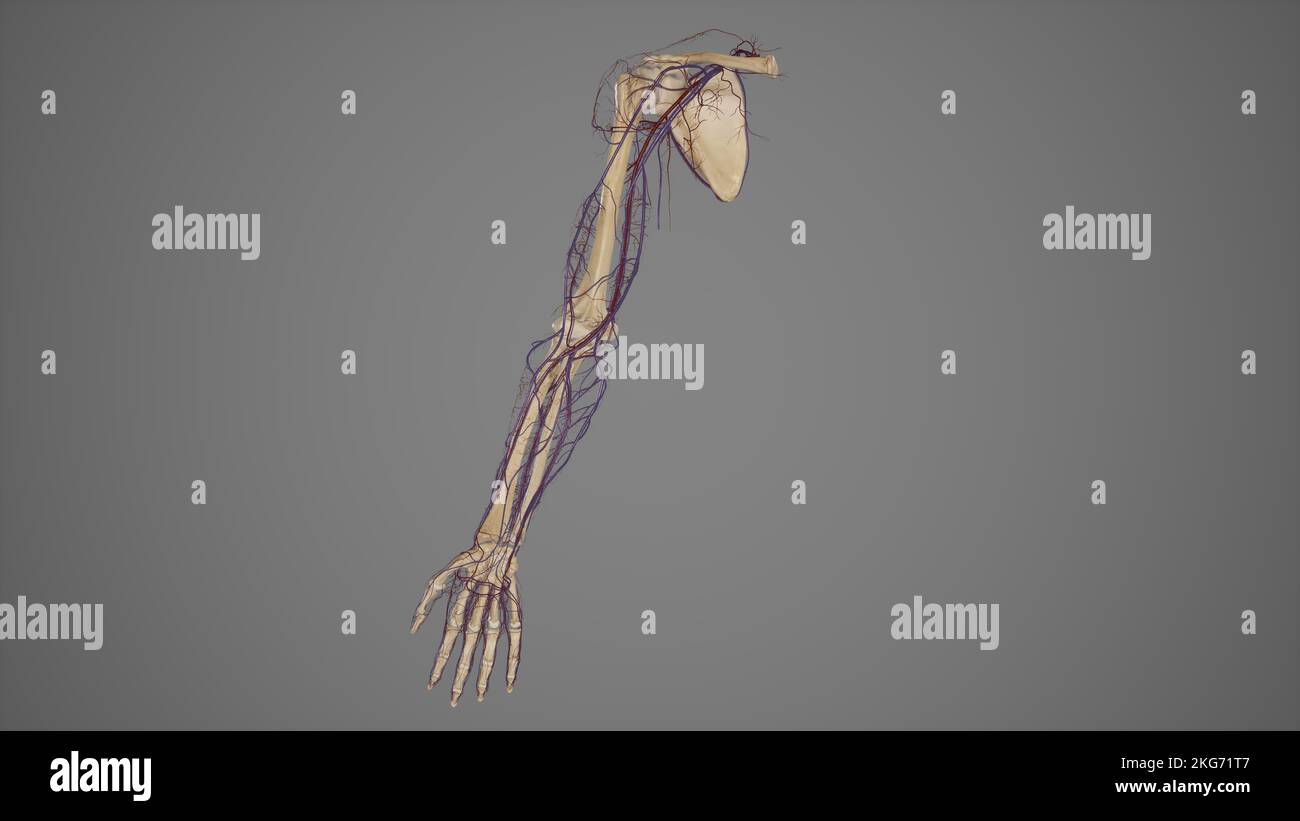

RF2KDED11–Arterielle Versorgung des vorderen und hinteren Beins über die Arteria poplitealis und ihre Zweige

RMETMN27–Darstellung der Blutversorgung und Skelett-Struktur der Unterschenkel, durch die Haut sichtbar.

RMETMNMF–Darstellung der Blutversorgung und Skelettsystem an den Unterschenkeln, durch die Haut sichtbar.

RMETMP9E–Darstellung der Blutversorgung und Skelett-Struktur der Unterschenkel, durch die Haut sichtbar.